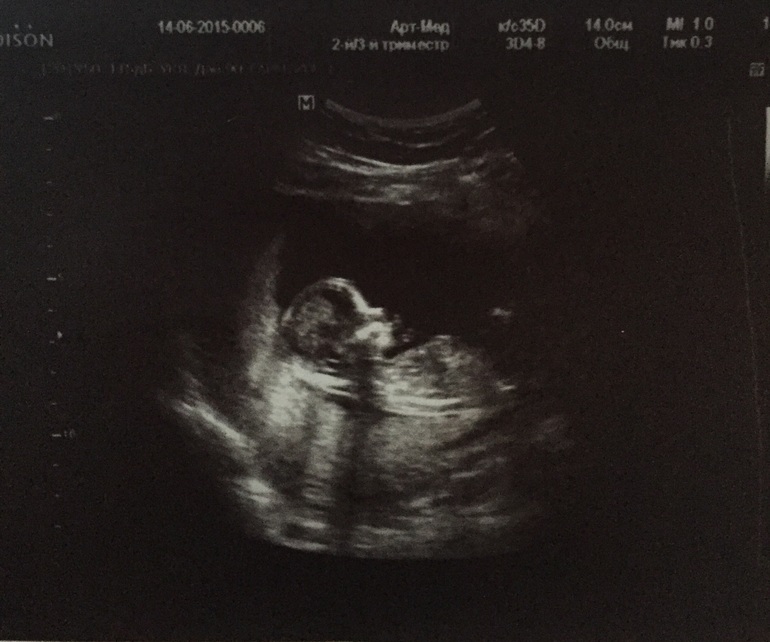

Были на узи .

Пол малышаВ арт меде всё хорошо срок 14 нед .

Ктр 78.3

Длина бедренной кости 10,6 мм

Масса плода 77 гр

Чсс 150 .

И тадам нам сказали пол у нас сыночек !!!!

И фото

Вот сфоткали доказательства, уж не знаю так или нет но вроде как мальчик , теперь в поисках имени ломаем головы ))))